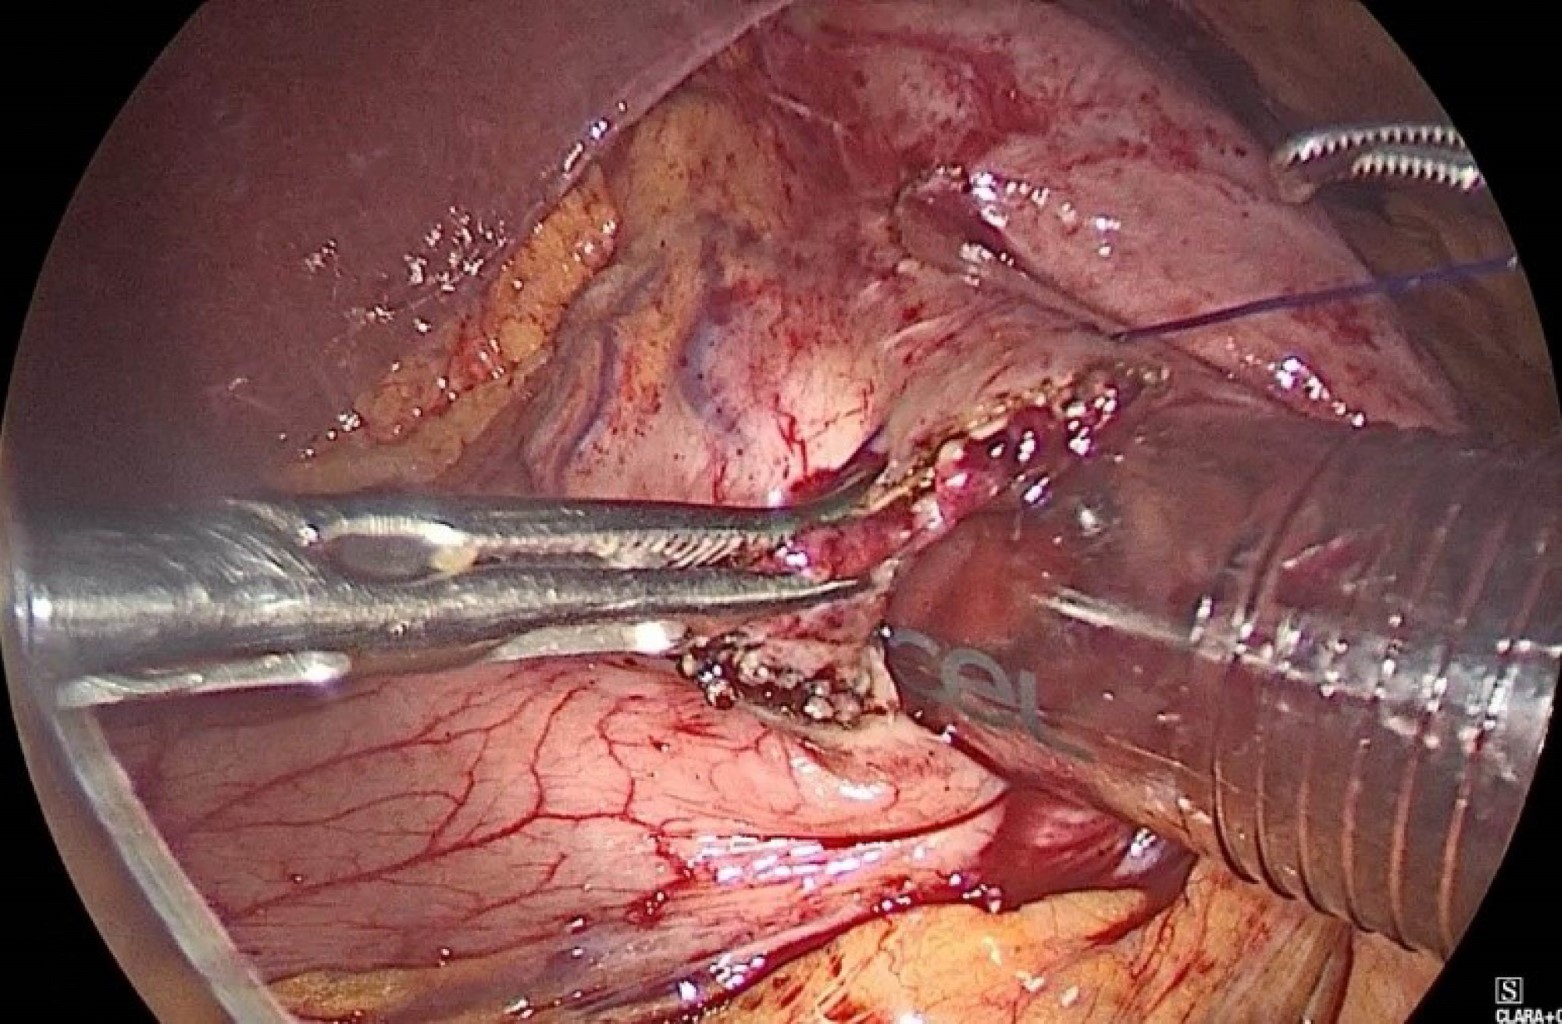

Se colocó a la paciente en decúbito supino con Trendelenburg invertido y bajo efectos de anestesia general, se insertó aguja de Veress en punto de Palmer, se inició neumoperitoneo y se colocó bajo visión directa primer trocar de 15 mm en región supraumbilical paramedial izquierdo seguido de tres trocares más, un trocar paramedial izquierdo de 15 mm colocado de 7 a 10 cm por encima del trocar óptico para la mano derecha del cirujano, trocar paramedial derecho de 5 mm, situado de 7 a 10 cm por encima del trocar óptico para la mano izquierda del cirujano y trocar de 12 mm en hipocondrio izquierdo para el ayudante. Se realizó jareta con PDS 2-0 en antro gástrico y posteriormente incisión gástrica (Figura 2), se insertó a través de gastrostomía el trocar de 15 mm (Figura 3) exteriorizando los hilos de sutura correspondiente a la jareta a través del mismo. El ayudante cirujano y endoscopista avanzó duodenoscopio por medio del trocar de 15 mm hasta segunda porción de duodeno y se observó papila alargada (Figura 4) con múltiples pliegues, posteriormente se canuló de manera selectiva la vía biliar con esfinterótomo y guía de alambre observando avance cefálico de guía, se instiló medio de contraste observando en colangiograma la vía biliar intra y extrahepática dilatada con conducto hepático común y colédoco proximal de 13 mm, colédoco medio 12 mm, colédoco distal de 10.5 mm con un defecto de llenado de 9 mm en su interior. Se realizó esfinterotomía y barrido mediante catéter con balón, se extrajo lito, líquido biliar y contraste. Se infló y ancló catéter con balón, se instiló medio de contraste observando vía biliar permeable sin defectos de llenado (Figura 5). Se procedió a retiro del instrumental con fluoroscopía de control con depuración adecuada de contraste de vía biliar. Se retiró duodenoscopio, se retiró trocar de 15 mm de la gastrostomía y se cerró en dos planos con sutura PDS 2-0 (Figura 6). Se colocó drenaje tipo Blake de 19 Fr hacia la gastrostomía y se exteriorizó por la incisión de trocar en hipocondrio izquierdo, se realizó cierre de heridas por planos y se finalizó el procedimiento sin haber presentado incidentes o complicaciones quirúrgicas. Durante sus primeros dos días de posoperatorio, se mantuvo sin dolor, toleró la vía oral, canalizó gases y el gasto por drenaje escaso con características serohemáticas, por lo que se retiró al segundo día y se decidió su egreso por mejoría, actualmente a varios meses de posoperada se encuentra sin complicaciones.

Figura 6